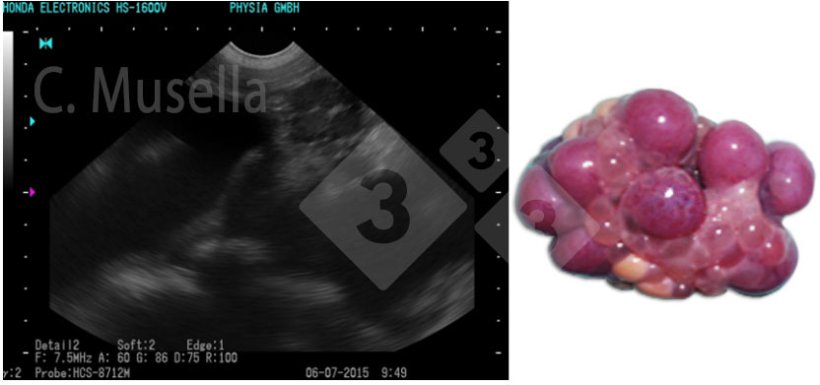

Rozpoznanie pojedynczych lub mnogich torbieli jajnika jest stosunkowo proste, nawet jeśli pełna identyfikacja typu torbieli na podstawie obrazu USG nie zawsze jest pewna.